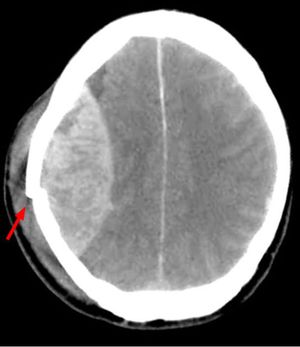

A 30-year-old male is brought to a trauma center by an emergency responder team after a vehicle accident. The patient was driving a motorcycle and collided with a bus. The EMT personnel found the patient alert with a short amnesia of the moments preceding the accident. In the ER, the patient is drowsy but still follows commands. Both his pupils are symmetrical and responsive to light with no other evident deficits. While the patient is being transferred from the computed tomography (CT) scanner room to observation floor, his level of consciousness declines to stupor, his left pupils became unresponsive to light, and his blood pressure rises to 190/110 mm Hg. His CT scan is given on the right. A.Tearing of the middle meningeal artery B. Dural arteriovenous fistula C. Tearing of bridging veins D. Charcot-Bouchard aneurysm E. Arteriovenous malformation

A, is an epidural hematoma, the temporal bone fracture is above the middle meningeal artery and the epidural hematoma looks like a lens on CT. The pacient worse because the epidural hematoma promote mass effect, with herniation of uncus, compressing the brainstem and lowering consciousness level. Without urgent surgery, the prognostic is bad. When the blood came from a vein rupture, the image shows blood above the brain, spread in the subdural space, and no circunscribed like this image. Charcot-bouchard aneurisms arn't seen in the CT, they are more likely to tease intracerebral bleeding, in the parenchima.